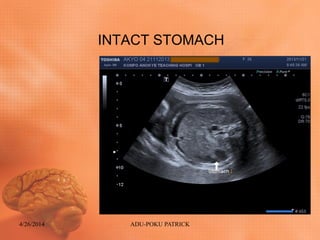

Ultrasound findings: ABDOMEN

• Diffuse skin thickening (Generalized body

Edema)

• Fetal Ascites

• Intact diaphragm

• Normal cord insertion

• Intact stomach

• Hepatomegaly

• Urinary bladder intact

INTACT STOMACH